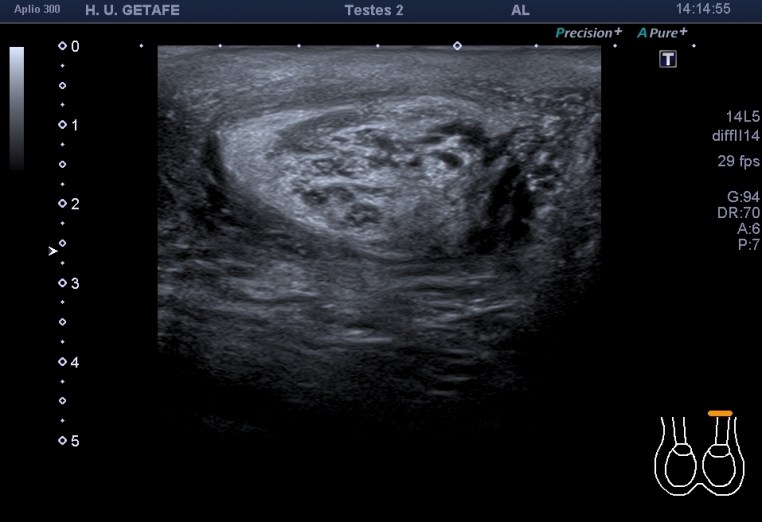

Se pide ecografía testicular por sospecha de hidrocele secundario a afectación del cordón por el tumor intraabdominal, a filiar. No se pudo poner contraste en el CT.

En la exploración observamos hidrocele unilateral izquierdo. En el canal inguinal puedes ver una estructura similar a una hernia inguinal, que con la maniobra de valsalva permanece inmóvil y por tanto no compatible con hernia a ese nivel de comportamiento normal y que podría estar provocando el hidrocele anteriormente referido.